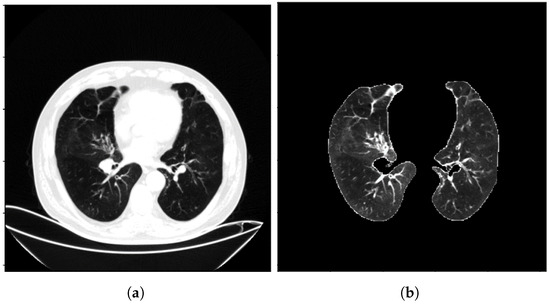

To increase the diversity of the samples, the 3D CT images underwent random rotations with angles within ±15 around the Z-axis of the CT images. Afterward, disease-related regions that might not be easily noticed by the network were cropped, and the cropped images were resized to pixels. For the experimental setup, the dataset was divided into a training set, validation set, and test set in a ratio of 3:1:1. This division ensured that the data were adequately represented for training, model validation, and final evaluation. To provide visual examples, Figure 1 illustrates the CT image data before and after the preprocessing steps, showcasing the impact of the normalization and cropping procedures. Figure 2 illustrates the CT image data before and after the preprocessing steps at a much larger scale.

Figure 1.

The CT image data before and after preprocessing, (a) is before preprocessing and (b) is after preprocessing.